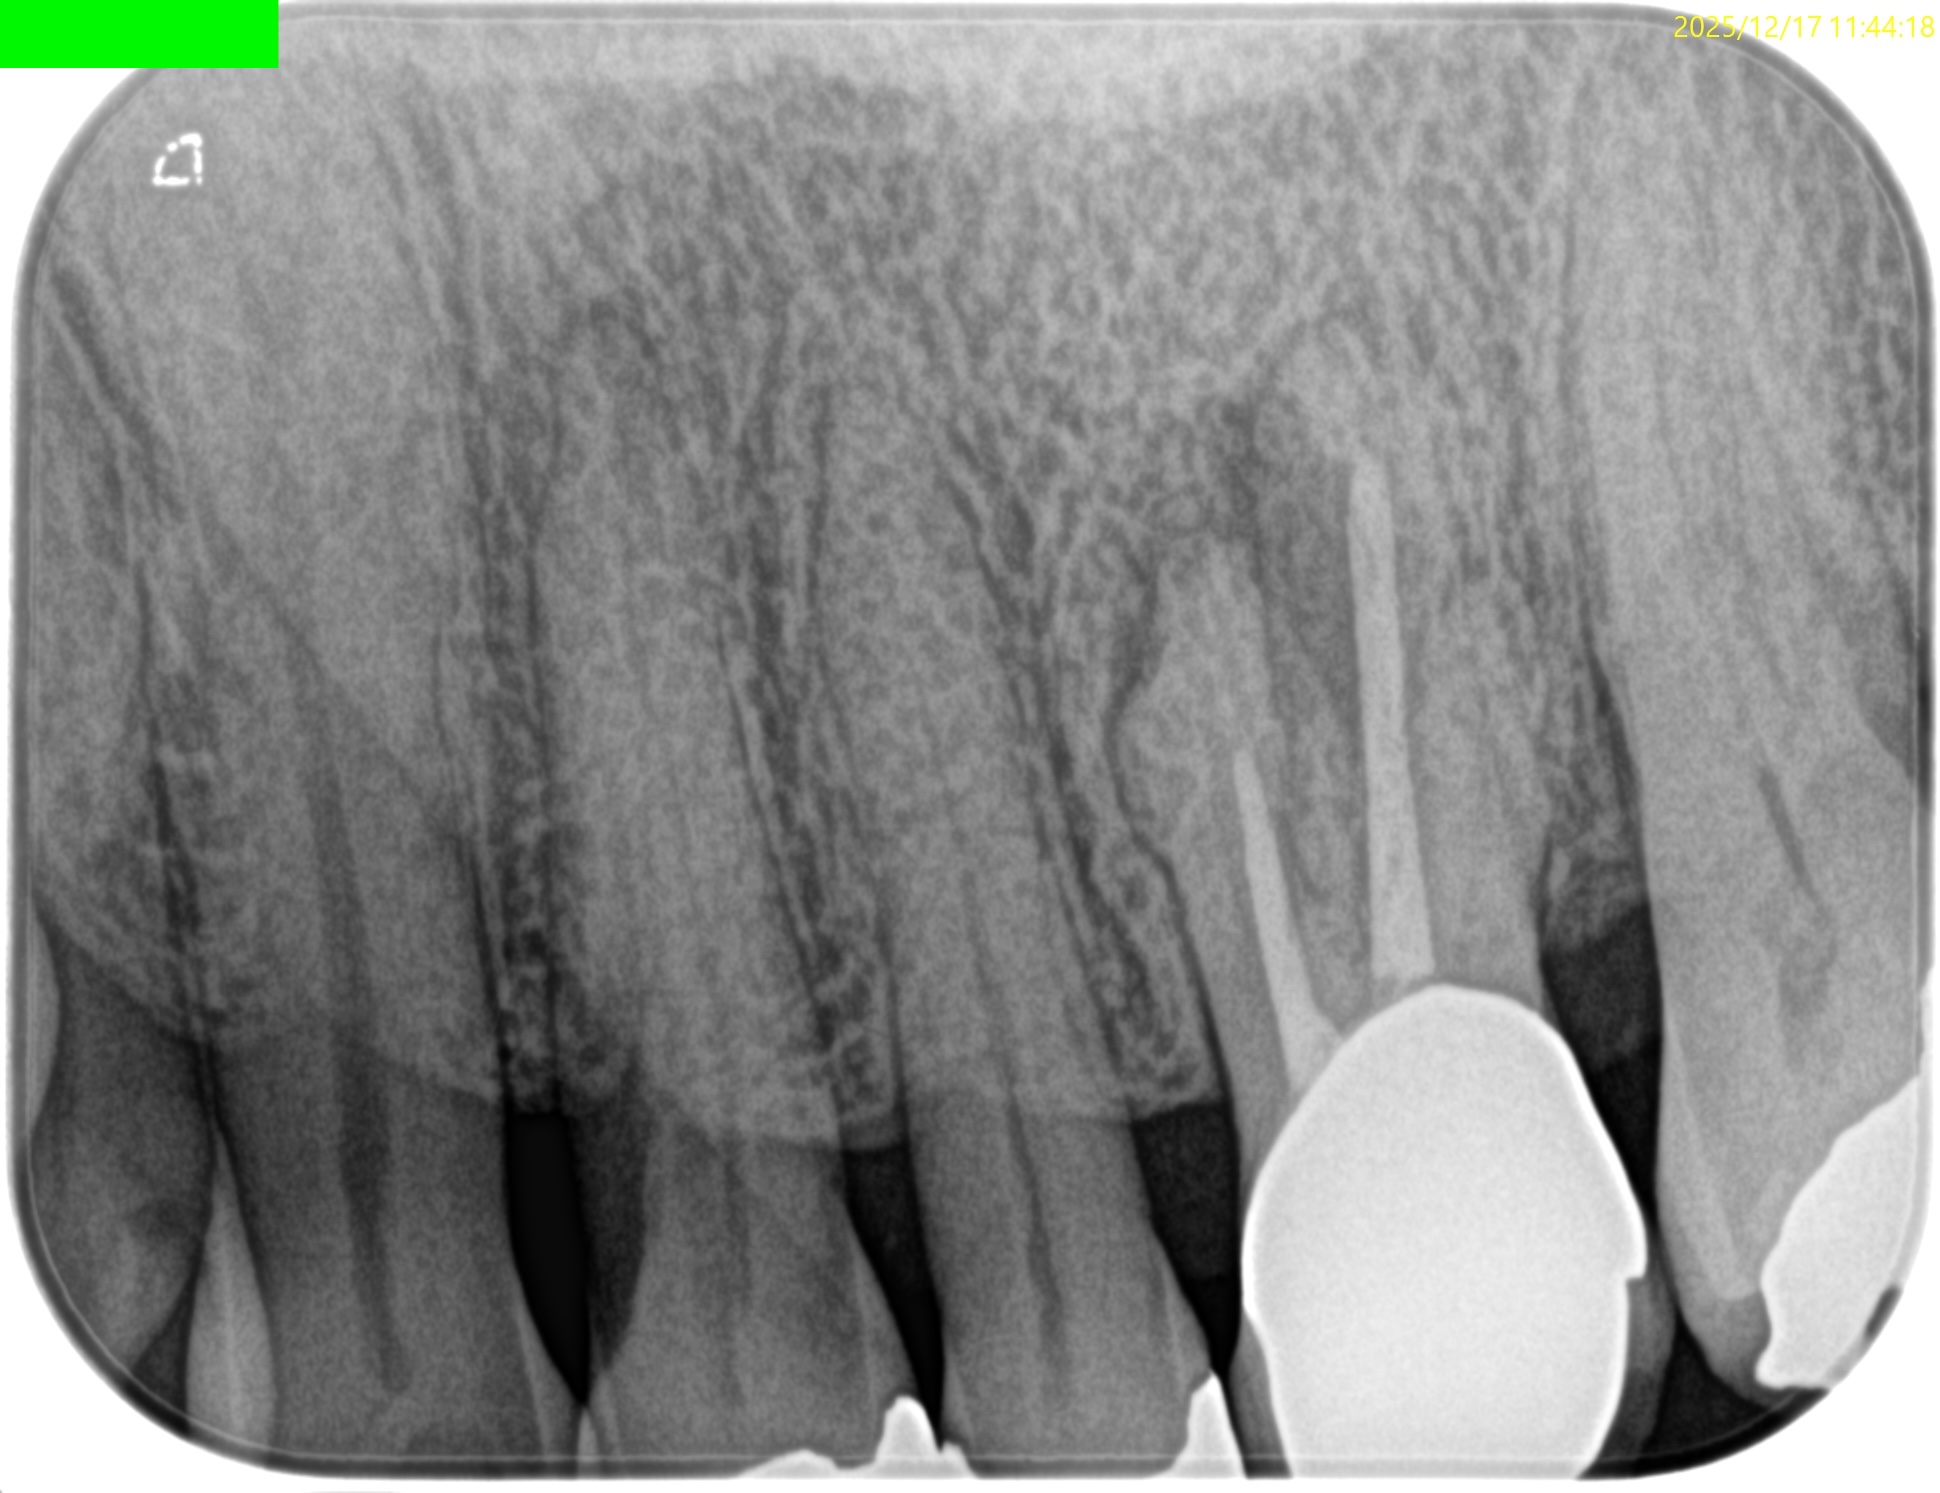

初診時は

私がまだGPで補綴も行っていた時代の契約書だ。

その時に装着したPFMは未だに脱離していない。

さておき、この同意書のPAではMB,DB,Pに根尖病変があるように見える。

が、CBCTがないので詳細がわからない。